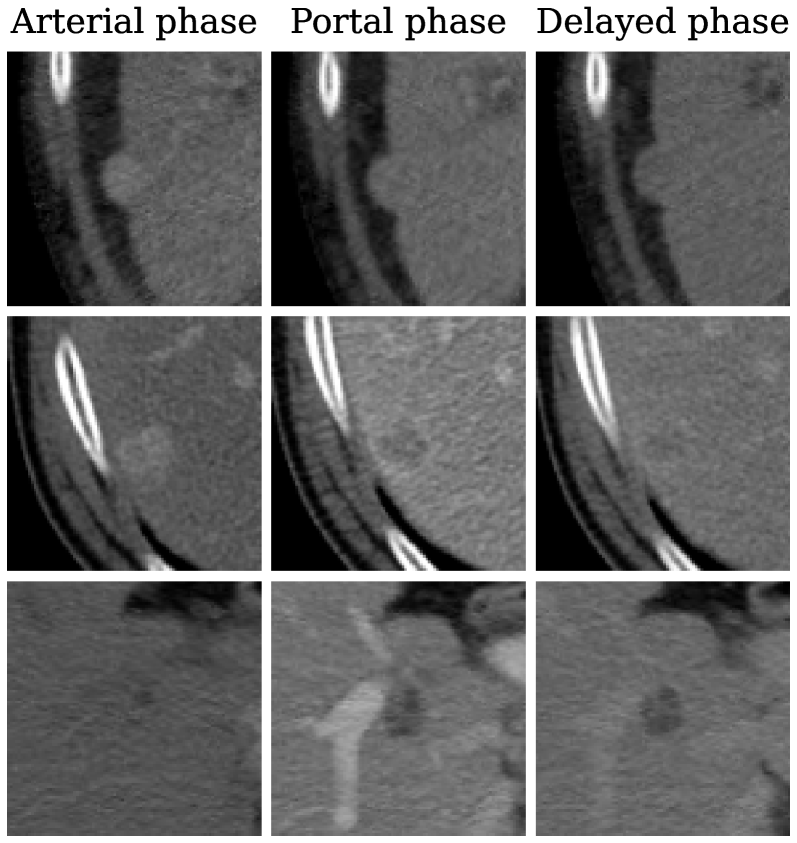

APHE: the arterial phase hyper-enhancement is defined by a contrast difference between the lesion and the liver parenchyma. This contrast is observed on the arterial phase and can be seen on the portal venous phase, as shown in Figure 2, lines one and two.

EC: the enhancing capsule is typically characterized by a thin enlightened contour with a darker inner lesion surface, as shown in Figure 2, at the second and third lines.

NPW: the non-peripheral washout corresponds to a decrease in attenuation or intensity from earlier to later phase, resulting in hypoenhancement in the portal venous or delayed phase, e.g a darkening of the lesion surface. It is observed at every line of Figure 2.

Fig. 2: Examples of center slices extracted from 𝒟1subscript𝒟1\mathcal{D}_{1}caligraphic_D start_POSTSUBSCRIPT 1 end_POSTSUBSCRIPT.